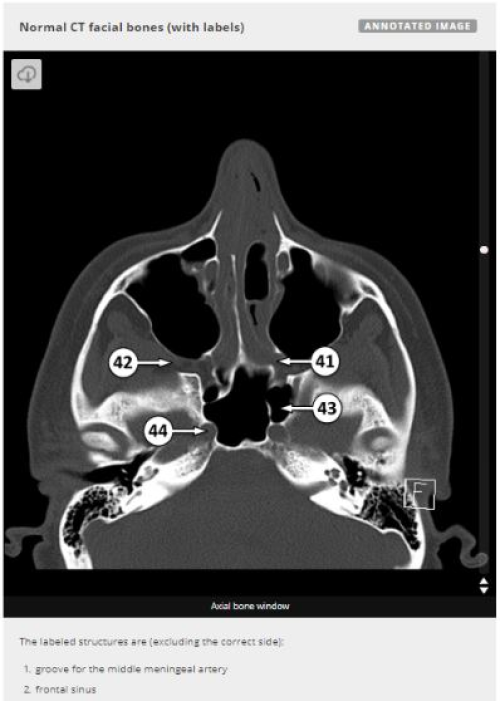

Best Online Resources to Improve Anatomy Knowledge Biology Diagrams Normal chest x ray. Radiological anatomy is where your human anatomy knowledge meets clinical practice. It gathers several non-invasive methods for visualizing the inner body structures. The most frequently used imaging modalities are radiography (X-ray), computed tomography (CT) and magnetic resonance imaging (MRI).X-ray and CT require the use of ionizing radiation while MRI uses a magnetic Radiology Masterclass - Provides an overview of medical imaging, complete with tutorials and access to images. Targeted at both medical students and other health professionals, this is currently a free UK resource. Topics include x-ray physics, anatomy visible in x-rays, and trauma x-rays.

e-Anatomy is a high-quality anatomy and imaging content atlas.It is the most complete reference of human anatomy available on the Web, iPad, iPhone and Android devices. Explore detailed anatomical views and multiple modalities (over 8,900 anatomic structures and more than 870,000 translated medical labels) with images in CT, MRI, radiographs, anatomical diagrams and nuclear images.